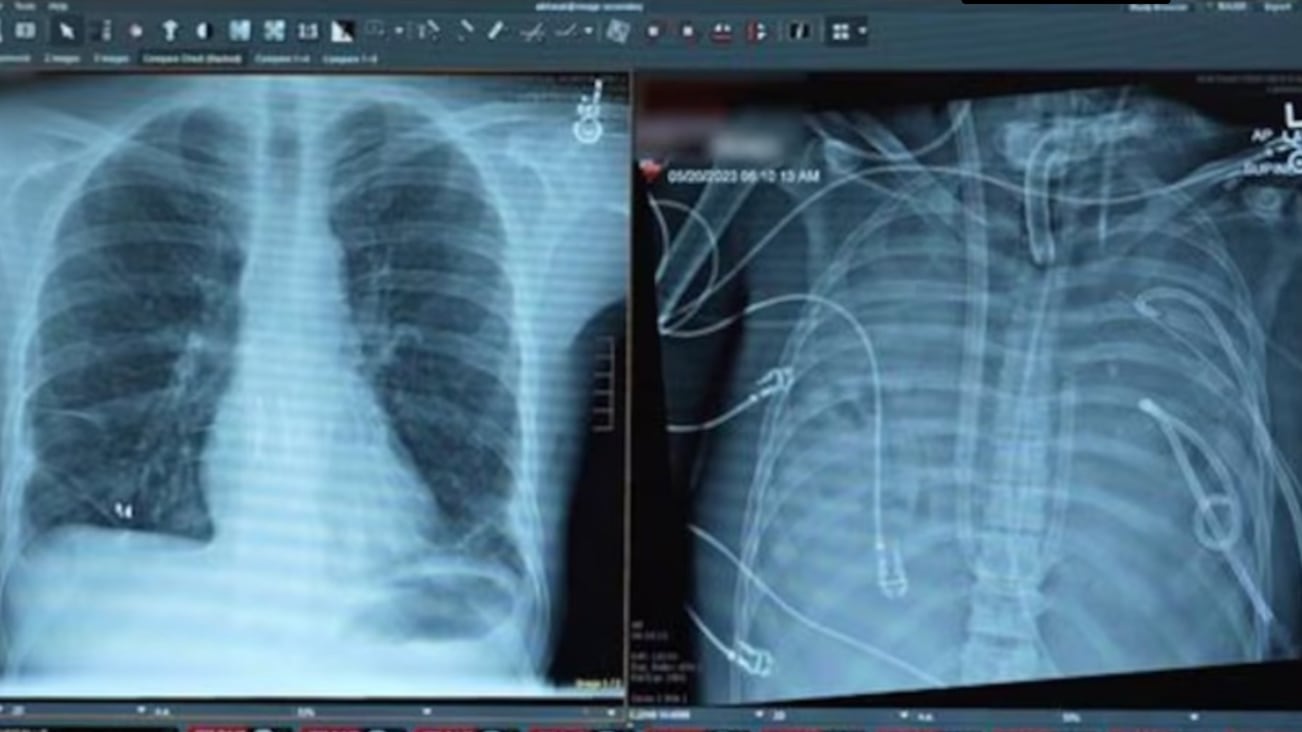

Pese al uso de ventilación mecánica y del sistema ECMO (oxigenación por membrana extracorpórea), el paciente continuó empeorando. Ante este escenario, los médicos tomaron una decisión extrema: extirpar completamente los pulmones infectados para eliminar el foco de la sepsis.

El mayor desafío era mantener con vida al paciente sin pulmones. Para ello, el equipo diseñó un sistema pulmonar artificial extracorpóreo capaz de oxigenar la sangre, eliminar el dióxido de carbono y mantener un flujo sanguíneo estable.

El dispositivo permitió estabilizar la presión arterial, evitar el colapso cardíaco y recuperar la función de otros órganos, mientras la infección disminuía progresivamente.

Gracias a este soporte artificial, el paciente se mantuvo con vida durante dos días sin pulmones, hasta que se consiguió un donante compatible. Entonces, los médicos realizaron con éxito un trasplante doble de pulmón.